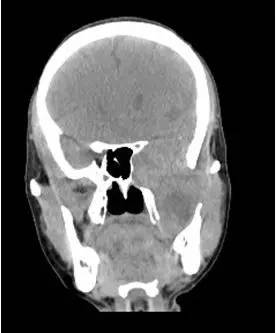

CT平扫冠状位重建

解析:本病例为中颅窝至颞下窝沟通性病变,对周围骨质主要呈膨胀压迫性改变,伴囊变、出血。